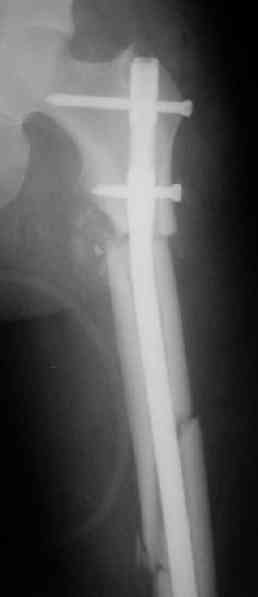

> денамизация - февраль 2006. ( 3 и 4 снимки) на сегодняшний день (снимок 5) беспокоит боли в тбс...

Однозначно: удалить, рассверлить, перештифтовать более толстым гвоздем. ЭТОТ 9 мм будет? Возьмите 12-14.

Дистально обязательно два винта! Проксимально можно один динамический. Больной будет счастлив на следующий же день!

Учитывая точку введения - верхушка б\вертела - что бы исправить варус взял бы соответствующий гвоздь: длинную Гамму или PFN или Recon